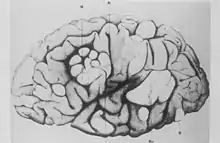

- نام عصبشناس فرانسوی دزیره مگلوآر بورنِـویل که بهطور تصادفی با این بیماری برخورد داشت، بر آن ماندگار شد. در آن هنگام، او به عنوان دستیار غیررسمی ژان-مارتن شارکو در بیمارستان پیتی-سالپترییر کار میکرد.[10] یک روز که بهجای استادش لویی دولاسیووْ کشیک میداد، بر بالین دختری ۱۵ ساله به نام ماری حاضر شد که دچار عقبماندگی حرکتی-روانی، صرع و «جوشهای عروقی، برجسته و بههم ملحقشونده بر روی بینی، گونهها و پیشانی» بود. این دختر از نوزادی سابقه تشنج داشت و در سن ۱۳ سالگی به بیمارستان کودکان برده شد و در آنجا گفته بودند که امیدی به درمانش نیست. او دچار مشکلات یادگیری بود و قادر به راه رفتن و حرف زدن هم نبود. هنگامی که ماری تحت مراقبت و درمان بورنِـویل بود، تعداد تشنجهایش بهشدت افزایش یافت و بهصورت انبوه رخ میداد. ماری را با شراب کینکینا، برومید کافور، آمیل نیتریت و قراردادن زالو در پشت گوشهایش، تحت درمان قرار دادند. ماری در ۷ مه ۱۸۷۹ در بیمارستان درگذشت. پس از کالبدگشایی، معلوم شد تکمههای سفت و سختی در مغز وجود دارد که بورنِـویل نامشان را «تصلبهای تکمهای چینهای مغز» نهاد. او گفت که اینها دلیل روی دادن صرعهای این دختر بودند. علاوه بر اینها، تودههای سفید و سختی «به اندازه یک گردو» در هر دو کلیهٔ او مشاهده شد.[12]

- پزشک ایتالیایی «جووانی باتیستا پلیتسی» دربارهٔ آسیبشناسی ضایعات مغزی تحقیق کرد. وی متوجهٔ ماهیت دیسپلاستیک آنها، دگرجایی قشر مغز[persian-alpha 2] و نقص در میلین شد. پلیتسی این تکمههای تصلبی را به دو گروه ۱ (با سطح صاف) و ۲ (با فرورفتگی مرکزی) تقسیمبندی کرد.[20][21]